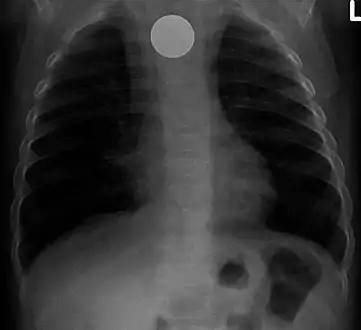

Both children and adults experience problems caused by foreign objects becoming lodged within their bodies. Young children, in particular, are naturally curious and may intentionally put shiny objects, such as coins or button batteries, into their mouths. They also like to insert objects into their ear canals and nostrils.[1] The severity of a foreign body can range from unconcerning to a life-threatening emergency. For example, a coin causes local pressure on the tissue but generally is not a medical emergency to remove. A button battery, which can be a very similar size to a coin, generates hydroxide ions at the anode and causes a chemical burn in two hours.[2] An ingested button battery that is stuck in the esophagus is a medical emergency. In 2009, Avolio Luigi and Martucciello Giuseppe showed that although ingested nonmagnetic foreign bodies are likely to be passed spontaneously without consequence, ingested magnets (magnetic toys) may attract each other through children's intestinal walls and cause severe damage, such as pressure necrosis, perforation, intestinal fistulas, volvulus, and obstruction.[3]

Foreign bodies in the peritoneum eventually become contained in a foreign body granuloma. In the extremely rare case of retained ectopic pregnancy, this forms a lithopedion, which involves the fetus being too large to be reabsorbed, and is calcified[13] as a means of shielding the surrounding tissue from infection.